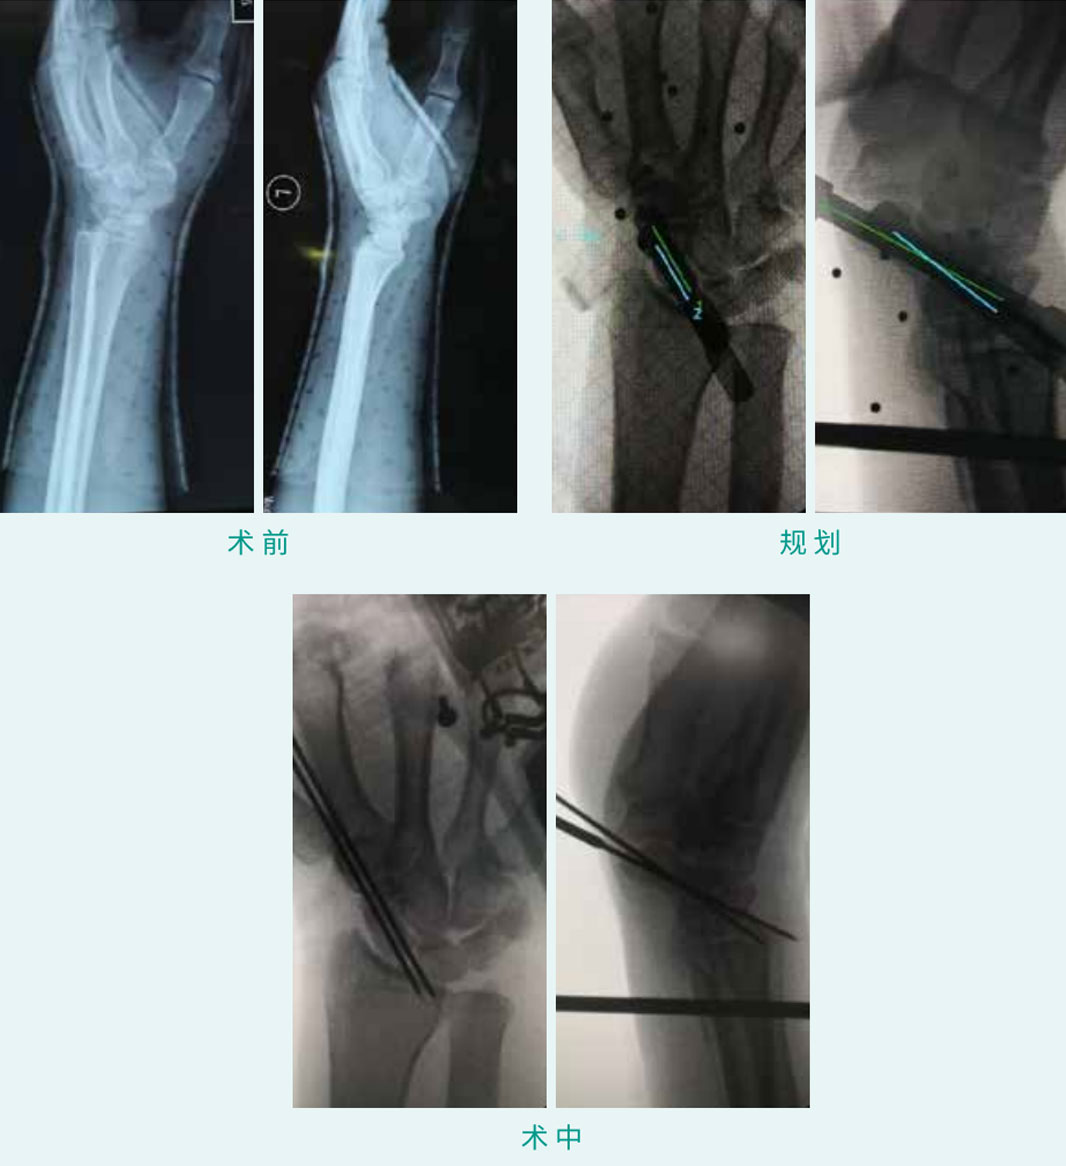

TiRobot ?  Scaphoid Fracture Percutaneous Screw Fixation

天玑? 辅助手舟骨骨折经皮空心螺钉内牢靠术

基本情形:患者男,30岁,手舟骨骨折

机械人累积用时:20分钟

植入物:2枚空心螺钉

病例泉源:北京积水潭医院 郭阳